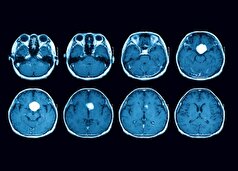

- مطالعه تکان دهنده: اضطراب و سرگیجه با تومورهای مغزی مرتبط هستند!